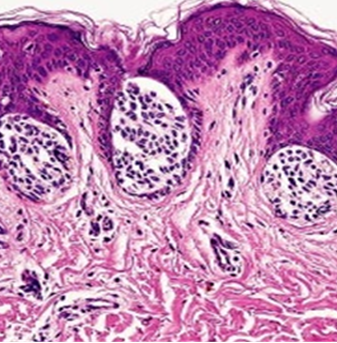

交界痣的黑素细胞聚集在表皮与真皮的交界处(即 皮肤的“基底膜带”之上),因此得名。临床特点为黑色或深褐色的斑点、小斑疹,边界清晰,色素均匀。初始可能针尖大小,渐渐扩大隆起,过渡成下面要讲的混合痣、皮内痣。

交界痣